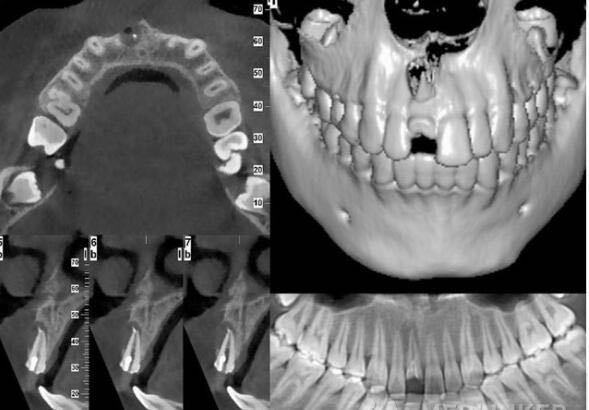

检查及结果:11残根,周围牙龈红肿,探(-),叩(++),冷热诊(-),松(0度) 辅助检查:X线示11根尖暗影较大,根管内见充填物 CT示11根尖唇侧骨板吸收,报告11根尖囊肿

诊断:11根尖囊肿 治疗方案:11试行根管再治疗+根尖手术 治疗过程:橡皮帐隔湿,显微镜下去除11根管内充填物,镍钛器械预备至F3,根管消毒。试尖发现11根管粗大,MTA充填根管下段4.5mm,6小时后热牙胶充填根管上段后行根尖手术,待患者伤口愈合后,制作临时修复体改善患者美观。嘱定期复查,3个 月后11根尖暗影明显减小,